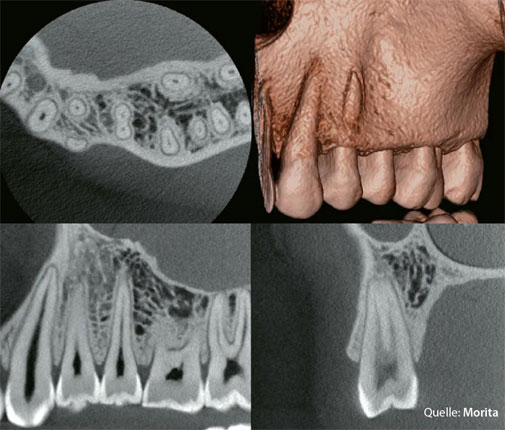

3D-DVT Befundbilder · Quelle: Morita

Präzise Darstellung von Wurzel­kanälen, Kiefer­knochen und Nerven­verläufen — Grundlage für eine sichere Behandlungs­planung und belastbare Diagnostik.

Ein DVT — Digitaler Volumentomograph — ist ein hochmodernes Röntgen­gerät, das ein drei­dimensionales Bild von Zähnen, Kiefer und den umliegenden Strukturen erstellt.